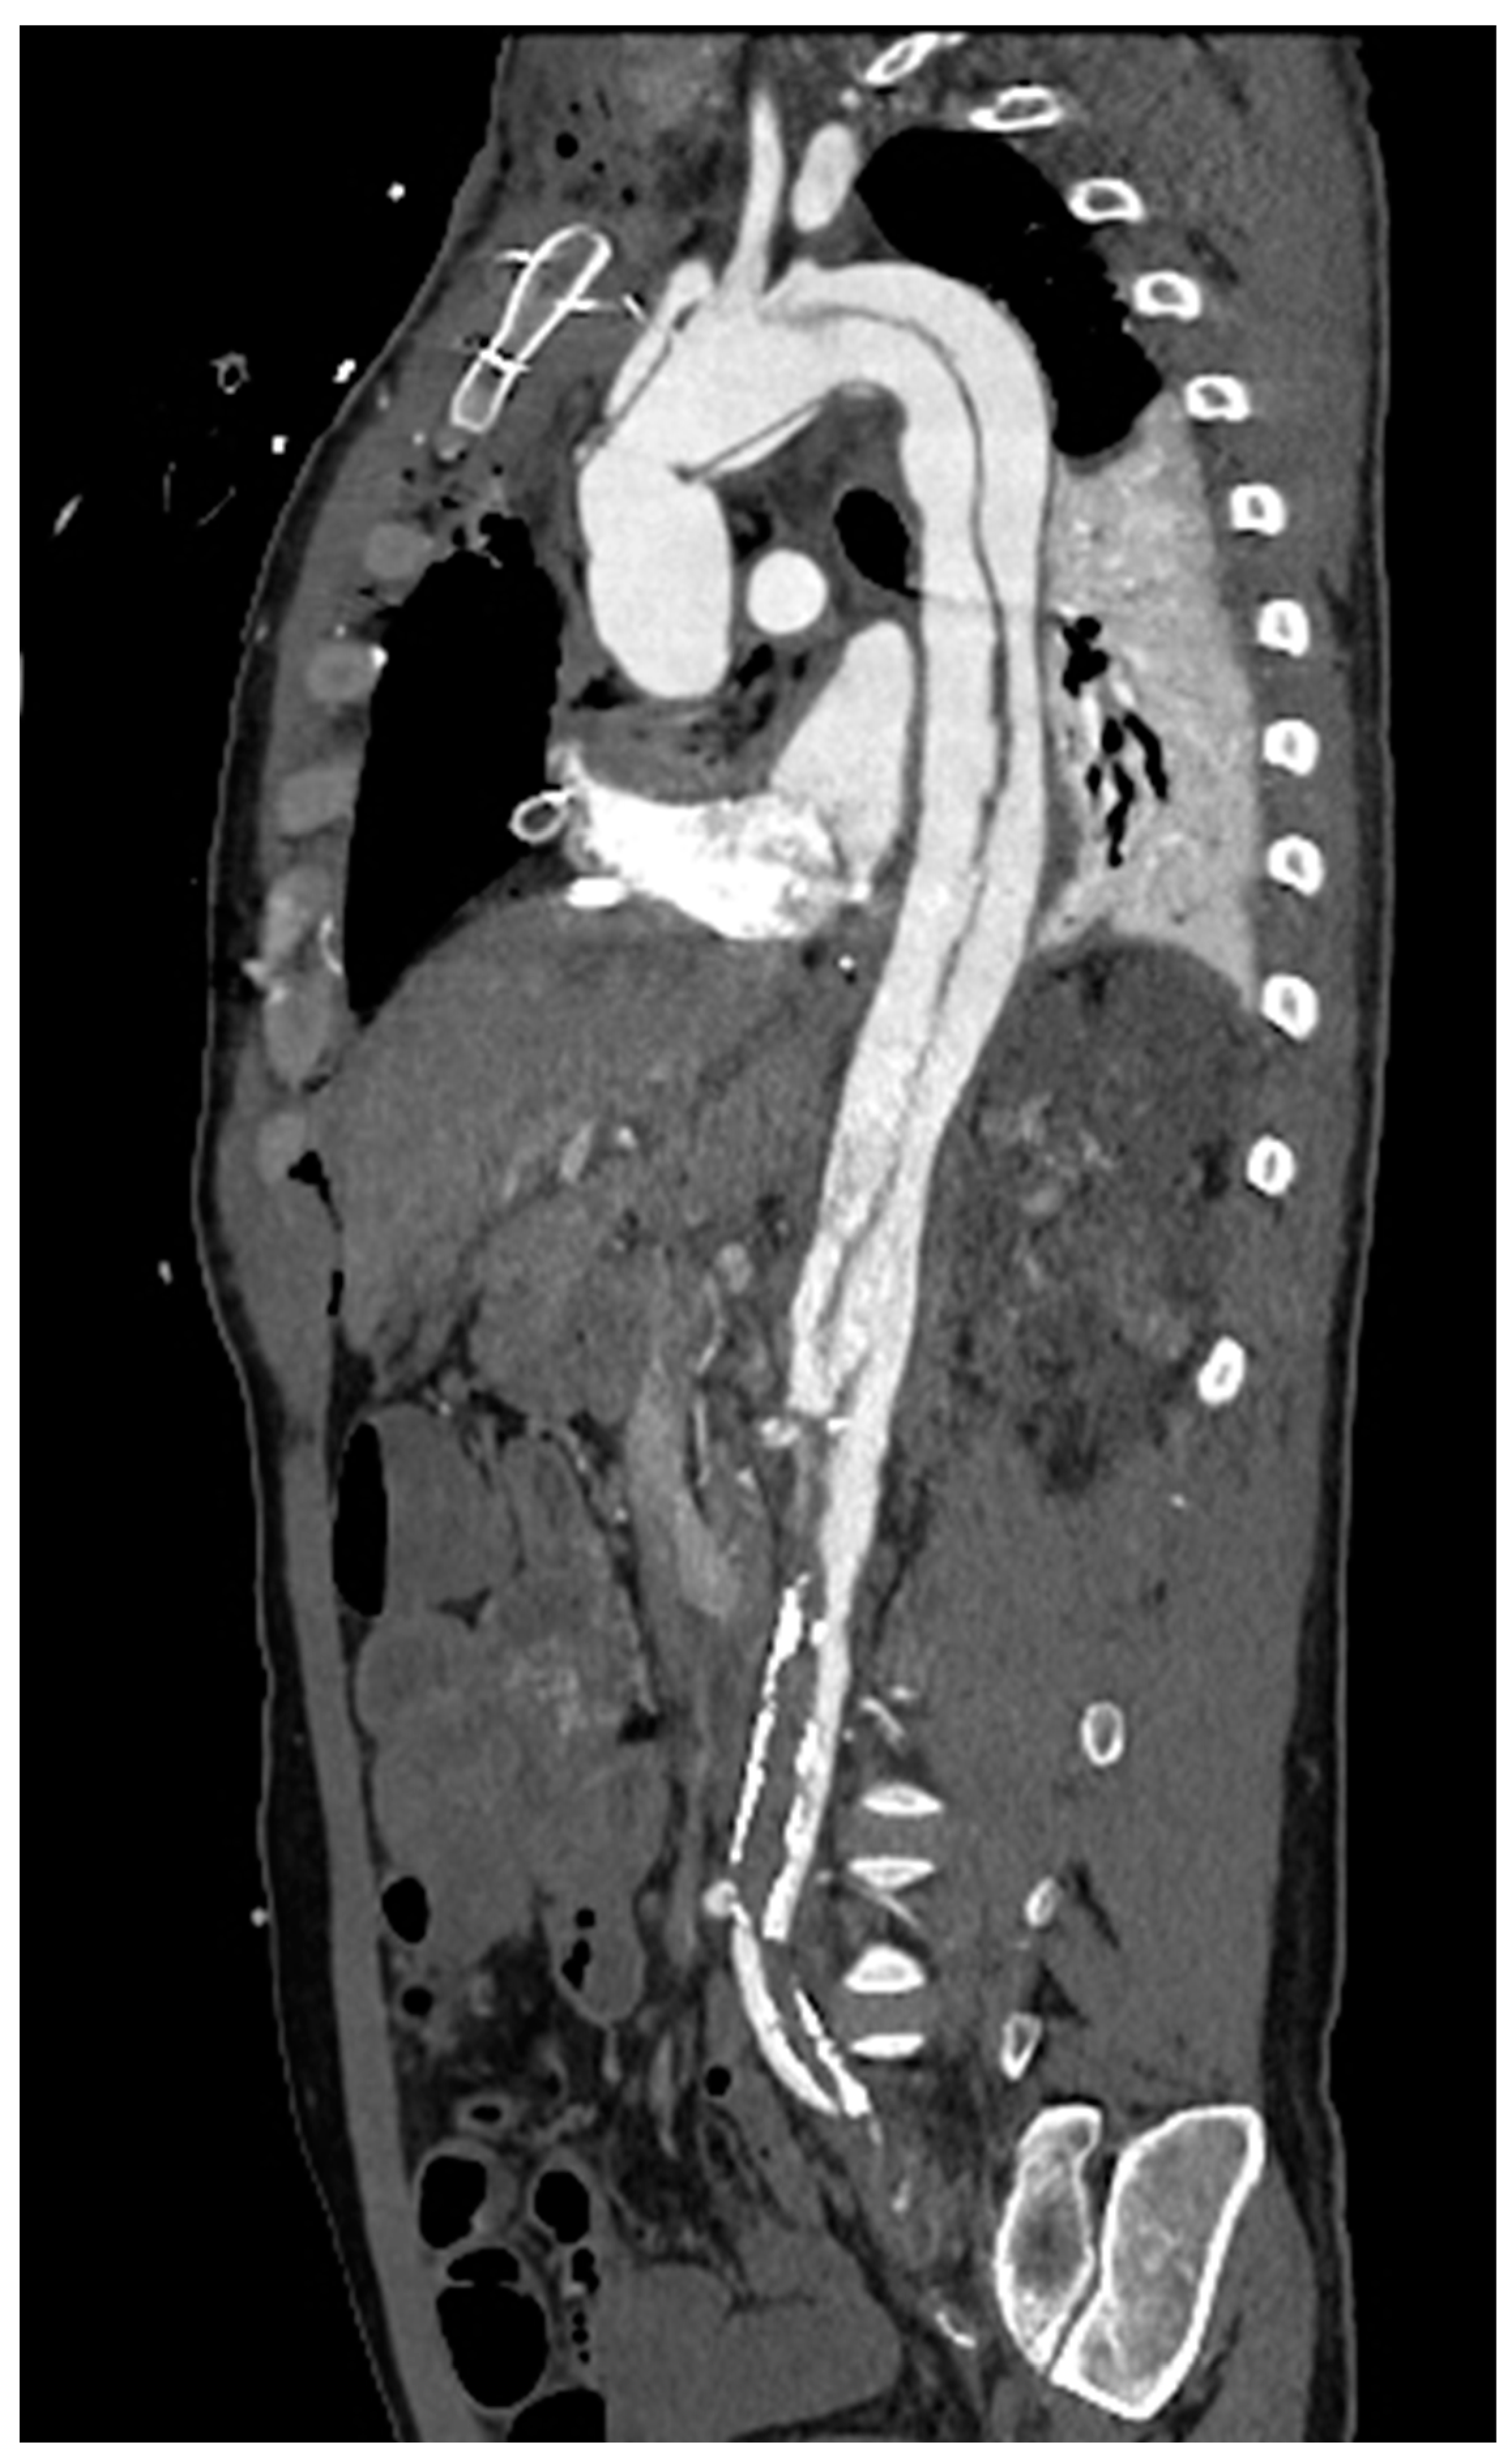

In Italy, CTA is the technique routinely employed in aortic imaging. Nowadays, multidetector row CT (MDCT) scans are highly efficient, widely available, and are highly sensitive and specific in diagnosing acute aortic syndromes (AAS) such as dissections, intramural hematomas, penetrating ulcers. Moreover, MDCT provides detailed insights into the vessel’s thickness and composition, allowing the evaluation of vasculitis and, in the emergency setting, it has been more and more employed to localize the sources of gastrointestinal bleeding(Geffroy et al., 2011). Maximum intensity projection (MIP) reconstruction provides global assessment and rapid detection of vascular stenosis and occlusion(Hyde et al., 2007). Pre-procedural MDCT is crucial for percutaneous interventions, such as transcatheter-aortic-valve-replacement and transcatheter -mitral-valve-replacement. While transthoracic echocardiography is often employed in monitoring post-procedure results with a limited acoustic window, potential complications are generally investigated by CT scans(Francone et al., 2020). In routine surgical scenarios, post-processing techniques, such as multiplanar reformats and segmented volume-rendered (VR) reconstructions, have greatly improved the assessment of vascular anatomy and they are generally requested by cardiac surgeons [Figure 5].

In a non-acute setting, MDCT has been traditionally preferred to Magnetic Resonance (MRI) because of its time consumption, inferior spatial resolution, and lower availability. However, the assessment of large vessels by Gadolinium-enhanced MRI is exponentially growing in the follow up in both pediatric and adult population, thanks to the latest advancements in MRI technology thanks to faster acquisitions and the advantage of being a ionizing free technique, with a specific diagnostic strength for tissue characterization (Pushparajah et al., 2019). Furthermore, MRI can give additional information on ventricular, valvular and vascular function and flow dynamics by using cine Steady-State-Free-Precession (SSFP) and Phase contrast sequences. Advancements in Fast-Spin-Echo (FSE) black-blood T1, Proton Density and Short-Tau-Inversion-Recovery (STIR) T2 sequences have improved the assessment of vessel, making them a valuable tool for aortic wall pathology [Figure 6](McNally et al., 2021).